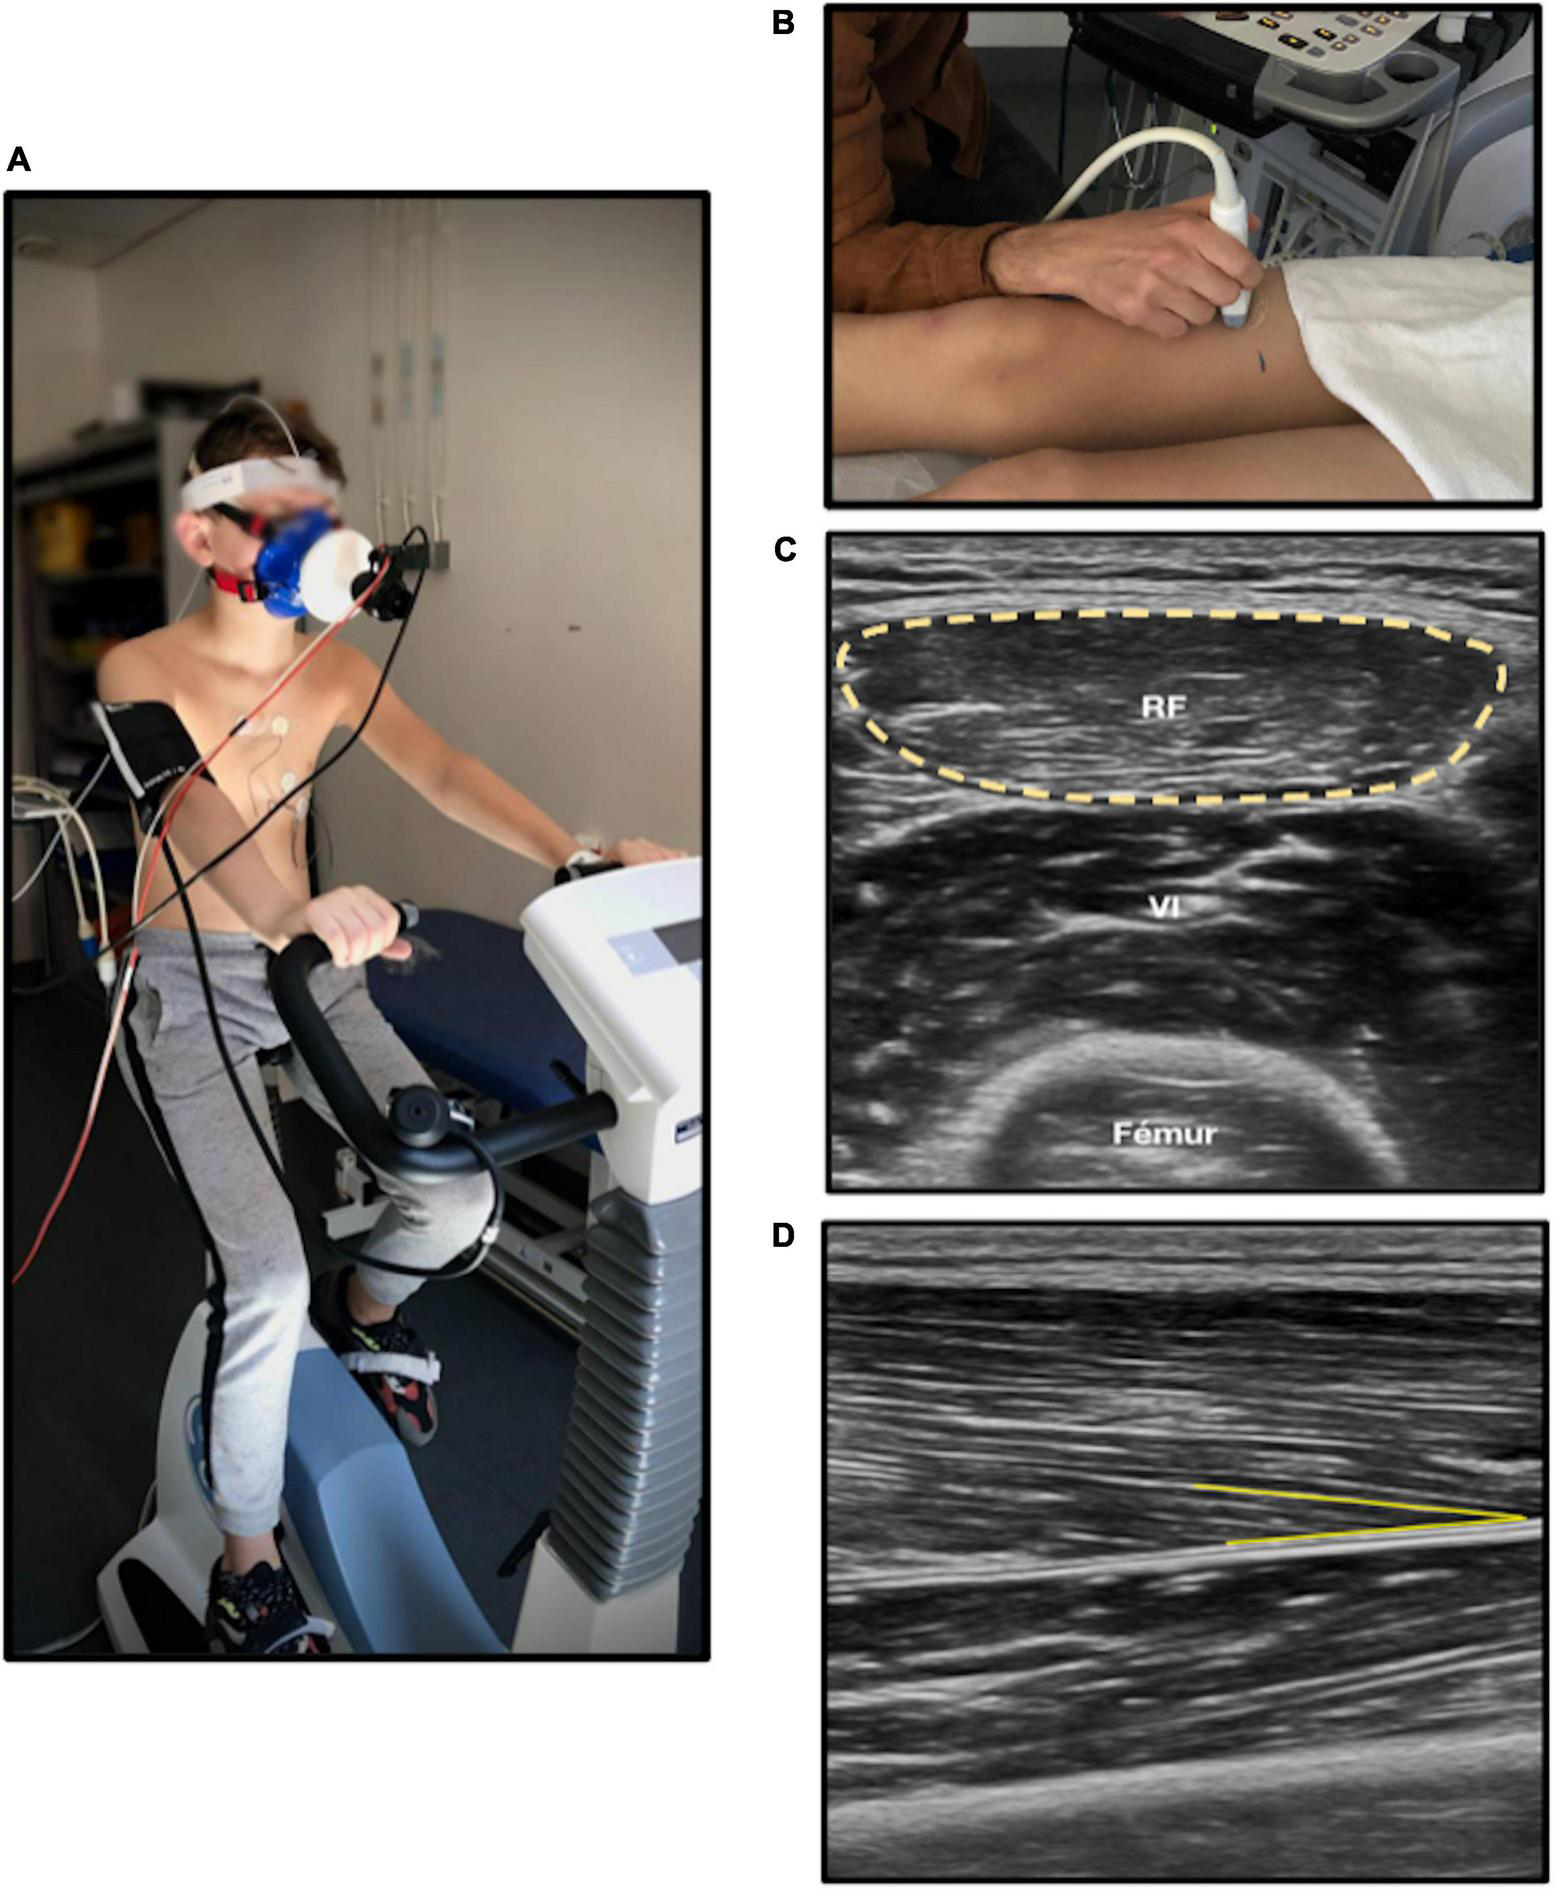

Muscle architecture reflects the contractile properties of muscle and is a determinant of strength capacity (33). It was evaluated by muscular ultrasound technique (34), the patient being in dorsal decubitus, with legs and arms relaxed, feet in neutral position, and arm in supination. Analyses of cross-sectional area on rectus femoris showed good feasibility and reliability (35). We measured two parameters: (1) the anatomical cross-sectional area on right rectus femoris, defined as the area of the cross-section of the muscle perpendicular to its longitudinal axis; (2) the pennation angle of vastus lateralis (Figure 1). Pennation angle was defined as the angle formed between muscular fascicles and intramuscular tendon insertion. A greater pennation angle enables more myofibrillar packing and promotes fascicle rotation during dynamic contraction strength, increasing muscle cross-sectional area and strength (36, 37). Thus, a lesser pennation angle may suggest reduced strength capacity (38). Five measures were performed for each one of the two parameters by a single operator. Minimal and maximal values were excluded, and the mean of the three remaining values was calculated. Image J software was used for image analysis. Muscular ultrasound examinations were performed using the EPIQ CVx (Philips®, Andover, MA, USA), and the Vivid E95 (General Electric®, New York, NY, USA).

FIGURE 1

Cardiorespiratory and muscle fitness analysis. (A) Cardiopulmonary exercise test on ergocycle. (B) Muscular ultrasound on right leg. (C) Anatomical cross-sectional area (yellow circle) of rectus femoris measured with ultrasound. (D) Pennation angle (yellow line) of right vastus lateralis; RF, Rectus femoris. The chosen anatomic site was at two third of the length from iliac spine anterior superior to upper edge of the patella on right leg. The probe was put in transversal plane and longitudinal plane for cross-sectional area and pennation angle, respectively.